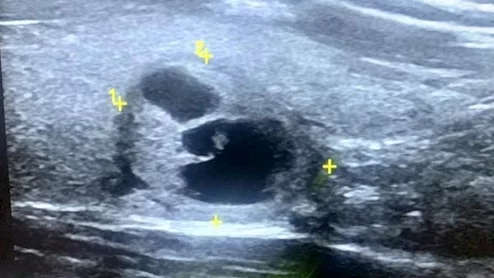

The new guidelines detail the use of echocardiography to evaluate patients for a variety of conditions.